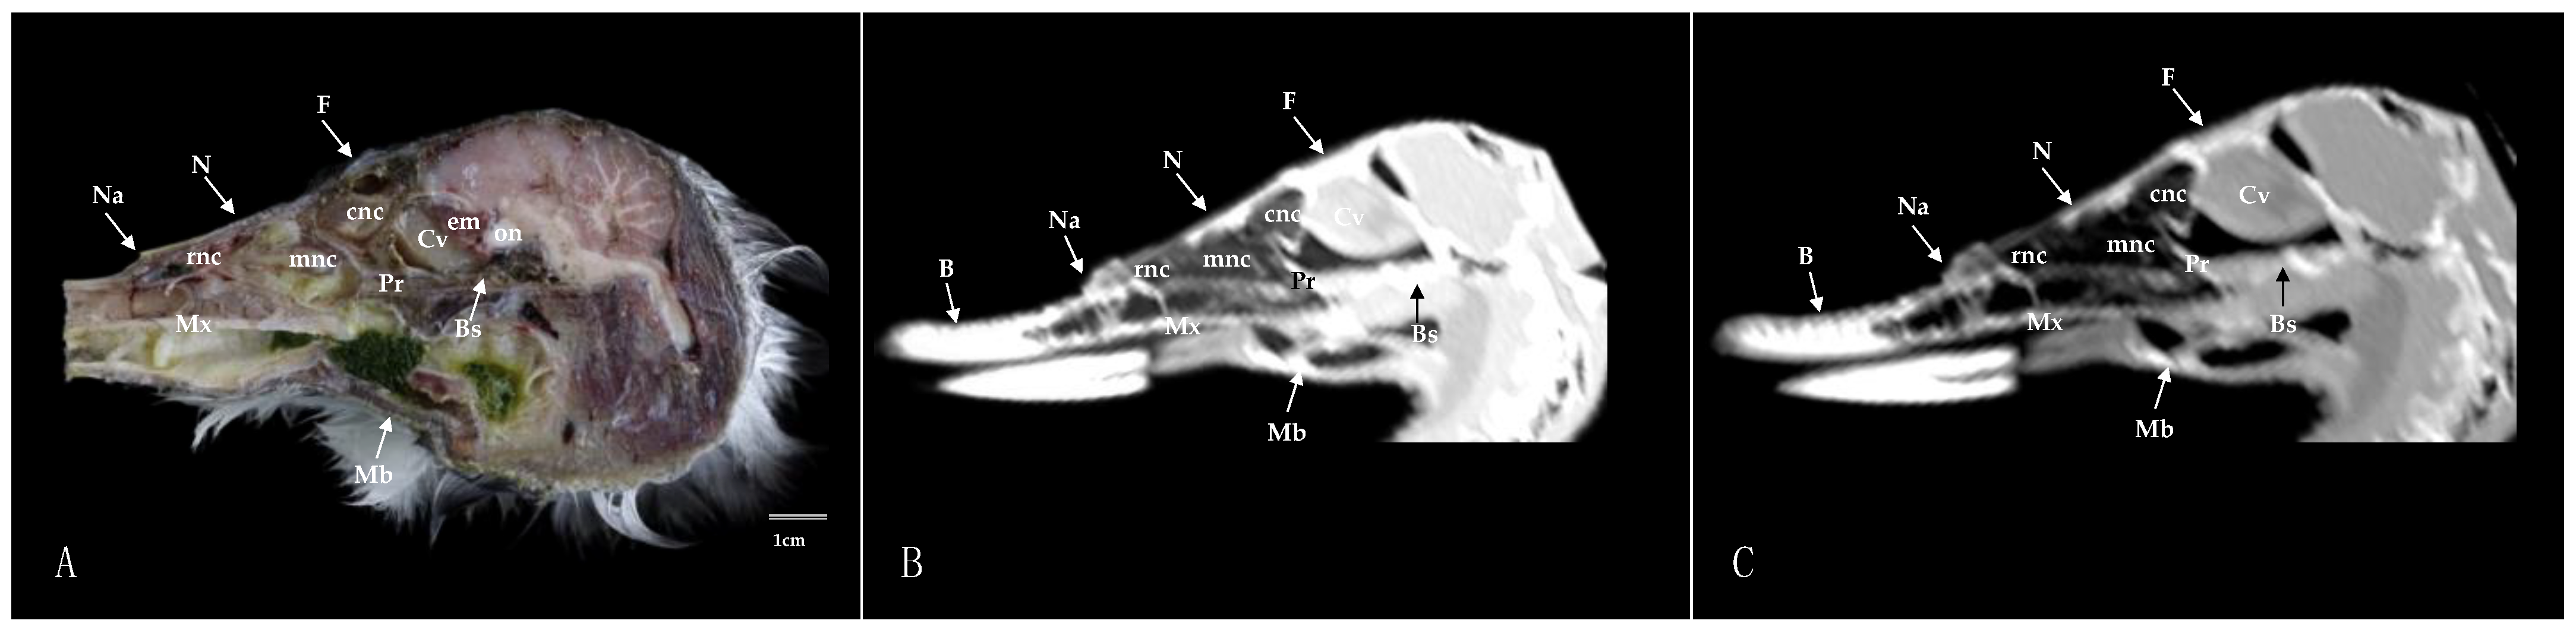

3.1. Anatomical Sections

3.2. Computed Tomography (CT)